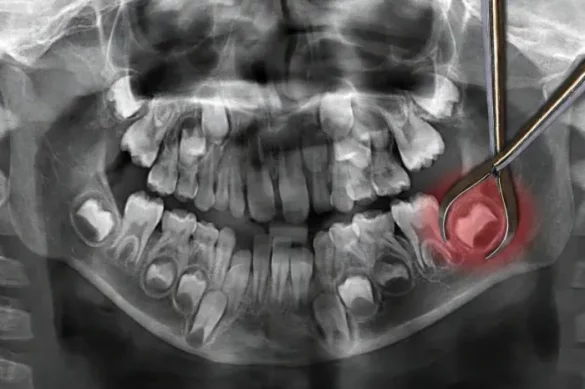

Wisdom teeth are your third set of molars, located at the back of your mouth. They usually appear between ages 17 and 21. For some, wisdom teeth grow in straight and do not cause problems. For others, they become impacted, which means there is not enough space for them to emerge or align with the rest of your teeth. This situation often leads to pain, infection, and damage to nearby teeth and gums.

In adults, wisdom teeth have fully developed roots. These roots may be long, thick, and sometimes curved. They might even grow near important nerves in the jaw. Extraction can be more technically complicated and carries a higher risk of affecting those nerves or nearby teeth.

Even for older adults, wisdom teeth can be extracted safely with proper planning. Your oral surgeon will take X-rays to examine tooth position, root development, and proximity to nerves. They may coordinate care with your physician if you have chronic conditions.

The area is numbed, and the dentist or oral surgeon removes the tooth. Sometimes the tooth must be divided or bone removed. After surgery, you will need to follow care instructions to heal well.

If you have pain, swelling, infection, or dental crowding, see your dentist. They will use exams and X-rays to decide if removal is the best choice.